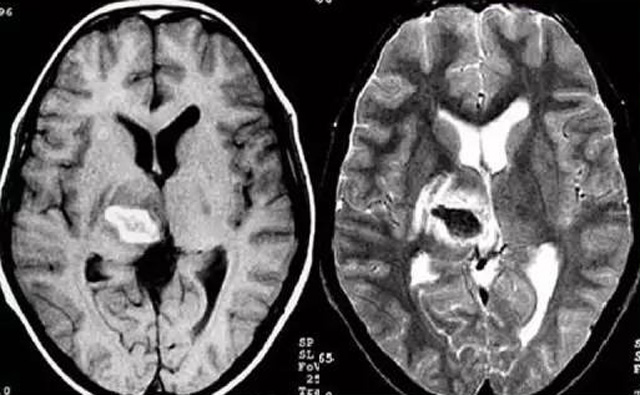

发现病人出血脑梗相关症状时候第一时间就医,需要携带以往的影像检查资料。向医生提供相关的病史基本资料。做影像检查时候需要全身不携带金属物品。检查时候身体保持不动,不然伪影对检查结果有干扰。磁共振MRI发现缺血性卒中后,帮助进一步查找病因。由于CT上小脑跟脑干颅骨影响,容易导致漏诊。MRI检查可以对CT检查不足的补充。短暂的脑缺血TIA也需要进行影像检查。短暂性缺血一般10几分钟后好转。检查目的可以确定TIA的病因。降低脑梗死的发生率。磁共振有助于排出TIA表现的颅内病变,有诊断及时治疗的价值。磁共振MRI检查时间比较长,不太适合急诊病人。但是可以发现脑干小脑的出血问题。因为急性脑梗死的早期和急性期,缺血区的脑组织还没有完全坏死,头颅CT不能显示病灶,所以就需要MRI磁共振检查,这个对陈旧跟亚急性出血显示比较好。缺点性价比不高,费用比较贵。头颅的磁共振MRI在发病后的几天CT的敏感降低时候发挥大作用。,MRI可作为诊断蛛网膜下腔出血和了解破裂动脉瘤部位的一种重要方法,必要时进一步进行DSA检查,帮助制订临床的手术治疗方案,

经颅多普勒超声(TCD)有效没有创伤性的检查方法,是检查脑血管的设备之一,它目前广泛应用于临床,检查判断脑出血卒中的头颅里面的内动脉外动脉的病变问题。诊断颅内动脉狭窄或闭塞性病变。颅外颈部动脉狭窄或闭塞性病变,评价颅外动脉严重狭窄或闭塞对颅内血流速度的影响。颈动脉内膜剥脱手术前预测夹闭作用、术后评估颅内血流变化。